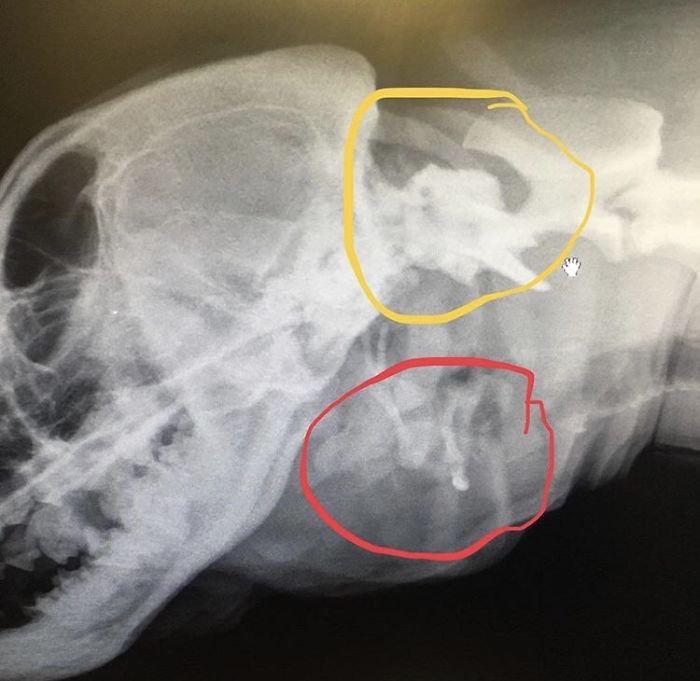

The 2nd mouth does not have any jaw so it cannot chew anything. It still produces saliva and is also connected with the original mouth. The extra mouth has three teeth which are cleaned by a vet often.

Despite her deformity, Toad is a healthy and sweet dog. Her X-rays also do not show any serious condition. The theory is that in the womb she might have absorbed one of her twins.